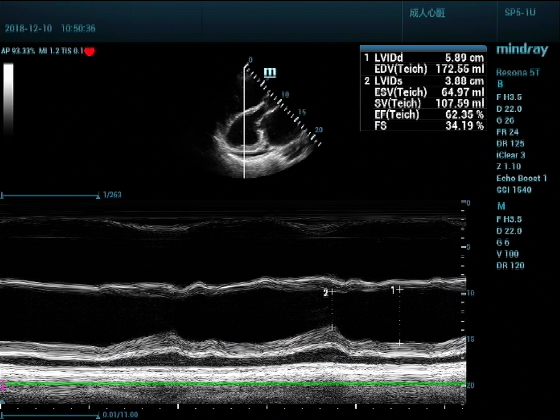

男,81岁,全身浮肿来住院

超声可见:左房,右房,右室明显增大,主肺动脉及右肺动脉增宽,二尖瓣中度反流,三尖瓣重度反流,肺动脉轻度高压,心律不齐

心包积液盆腔积液。淤血性肝增大,肝静脉增宽。(右心衰声像改变)